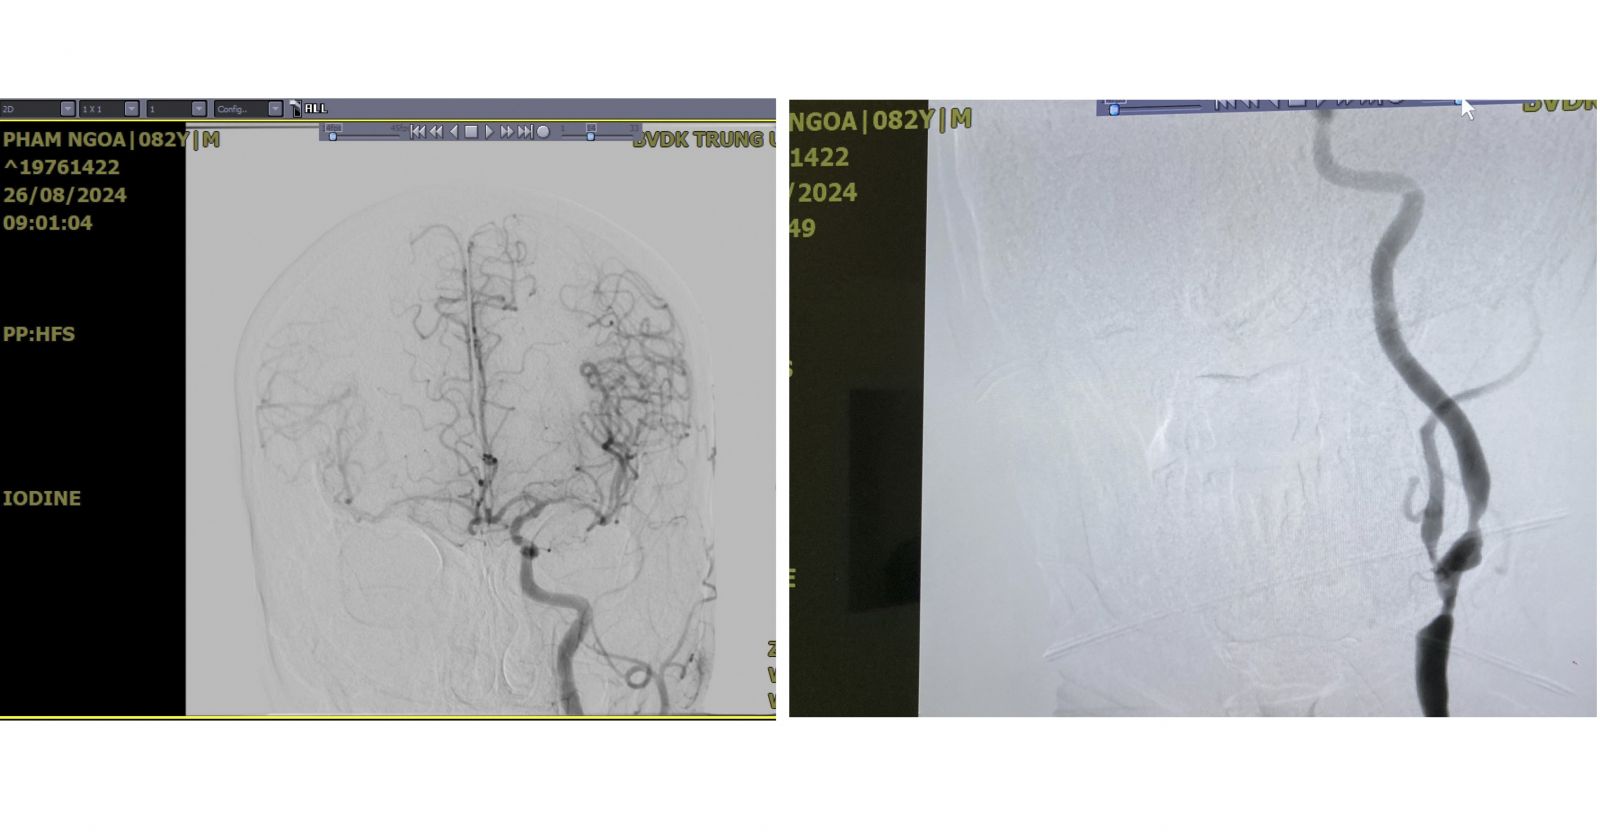

Hình ảnh chụp DSA trước phẫu thuật của người bệnh Phạm Ngõa cho thấy hai bán cầu đại não được cung cấp chỉ duy nhất 1 động mạch cảnh trái đang bị hẹp nặng.

Theo đó, người bệnh Phạm Ngõa (82 tuổi, trú huyện Bình Sơn, tỉnh Quảng Ngãi) đến khám tại Khoa Nội Tim mạch, Bệnh viện Đa khoa Trung ương Quảng Nam với kết luận mắc bệnh tắc động mạch cảnh 1 bên, hẹp động mạch cảnh 1 bên và bệnh lý 3 thân mạch vành.